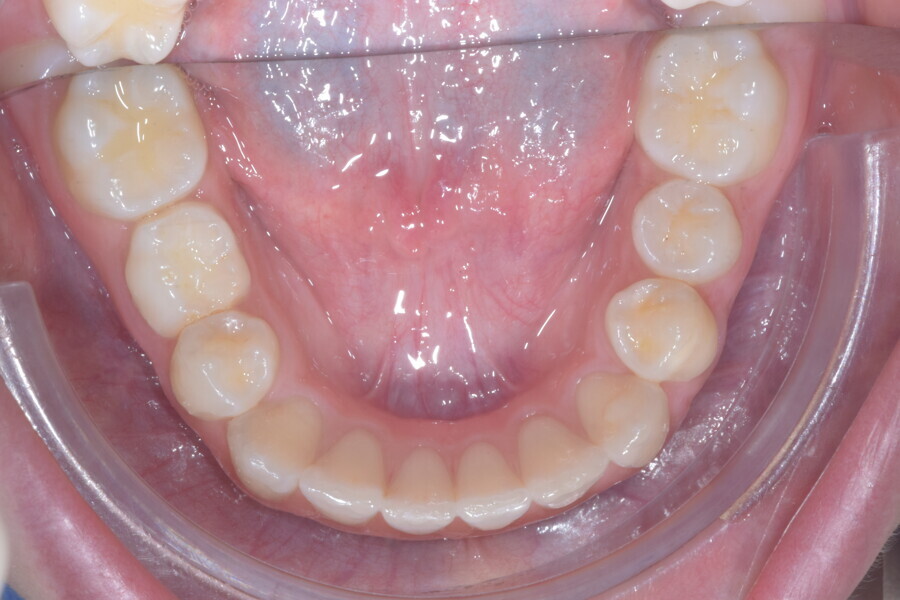

A 14-year-old female patient presented with the chief complaint of midline deviation and dental crowding in both arches. Facial analysis showed a hypodivergent growth pattern, a normal nasolabial angle, a harmonious profile and proper chin projection. Clinical examination revealed a Class III skeletal relationship (ANB = 0°) and Class I molar relationship. The maxillary right canine was absent, and this had led to space loss and mesial drift of posterior teeth on the right side, resulting in a slight Class II molar relationship. The maxillary left canine had erupted in a high position. The mandibular arch displayed crowding despite the agenesis of the right second premolar and the persistence of the primary molar (Figs. 3–11). The radiograph showed the probably premature loss of the maxillary right primary canine and consequently impacted maxillary right permanent canine, and the agenesis of the mandibular right second premolar and the mandibular right third molar (Fig. 12).

Cephalometric analysis showed normal incisor inclination (U1–PP = 112°) and slightly uprighted mandibular incisors (IMPA = 88°), consistent with dental compensation commonly observed in Class III skeletal malocclusions. Cephalometric analysis confirmed a reduced lower anterior facial height associated with a hypodivergent pattern (Figs. 13 & 14).